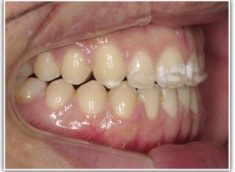

開咬(かいこう:オープンバイト)ケース

治療法:表の矯正(T21ブラケット)

(インプラントアンカーや外科矯正は行わず、エラスティックと機能訓練のみ)

治療前